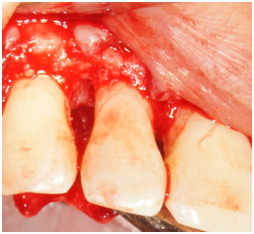

A decision was made to begin phase II therapy that included regenerative surgery using enamel matrix derivative to treat the increased probing depth of 10mm and bony defect on the disto-facial of tooth #26. The rationale for treatment was discussed with the patient and he was informed of the regenerative material and its origin. Because the intrabony defect around tooth #26 was isolated, an endodontic consultation was requested and the likely absence of a root fracture or pulpal pathology was confirmed. No other contributory factors were noted at the baseline examination. The patient was informed of the risk of tissue recession postoperatively as part of the written consent process. The patient was appointed to undergo the surgery that was carried out as follows: Local anesthesia with 2% lidocaine with 1:100,000 epinephrine was administered at the site of the surgery followed by intrasulcular incisions that were made from mesial of tooth #23 to mesial of tooth #29. A full thickness mucoperiosteal flap was reflected both facially and lingually to give good access to the defect site. The bony defect was identified and all the granulomatous tissue was removed and the root surface was debrided with ultrasonic and hand instruments. The bony defect was a two-wall defect (Figure 8). The root surface was examined for any abnormality or fracture and none was noted. EDTA and enamel matrix derivative‡‡ was applied to the defect according to the manufacturer instructions. The flap was secured back with interrupted 4-0 chromic gut sutures. Post-operative instructions were given to the patient both written and verbally. The patient was instructed to take pain medication (ibuprofen) as needed and to use chlorhexidine 0.12% as a mouth rinse. The patient was seen 1 week following surgery and the sutures were removed.

Figure 8 Facial view of tooth #26. Reflection of a full-thickness flap showing the bony defect on the distal-facial aspect.